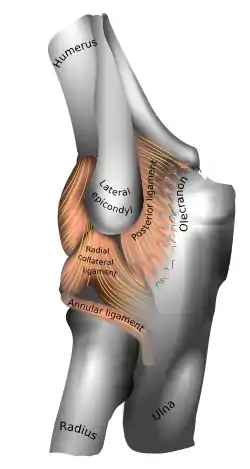

Ligaments

Left: anterior and ulnar collateral ligaments

Right: posterior and radial collateral ligaments

The elbow, like other joints, has ligaments on either side. These are triangular bands which blend with the joint capsule. They are positioned so that they always lie across the transverse joint axis and are, therefore, always relatively tense and impose strict limitations on abduction, adduction, and axial rotation at the elbow.[8]

The ulnar collateral ligament has its apex on the medial epicondyle. Its anterior band stretches from the anterior side of the medial epicondyle to the medial edge of the coronoid process, while the posterior band stretches from posterior side of the medial epicondyle to the medial side of the olecranon. These two bands are separated by a thinner intermediate part and their distal attachments are united by a transverse band below which the synovial membrane protrudes during joint movements. The anterior band is closely associated with the tendon of the superficial flexor muscles of the forearm, even being the origin of flexor digitorum superficialis. The ulnar nerve crosses the intermediate part as it enters the forearm.[8]

The radial collateral ligament is attached to the lateral epicondyle below the common extensor tendon. Less distinct than the ulnar collateral ligament, this ligament blends with the annular ligament of the radius and its margins are attached near the radial notch of the ulna.[8]